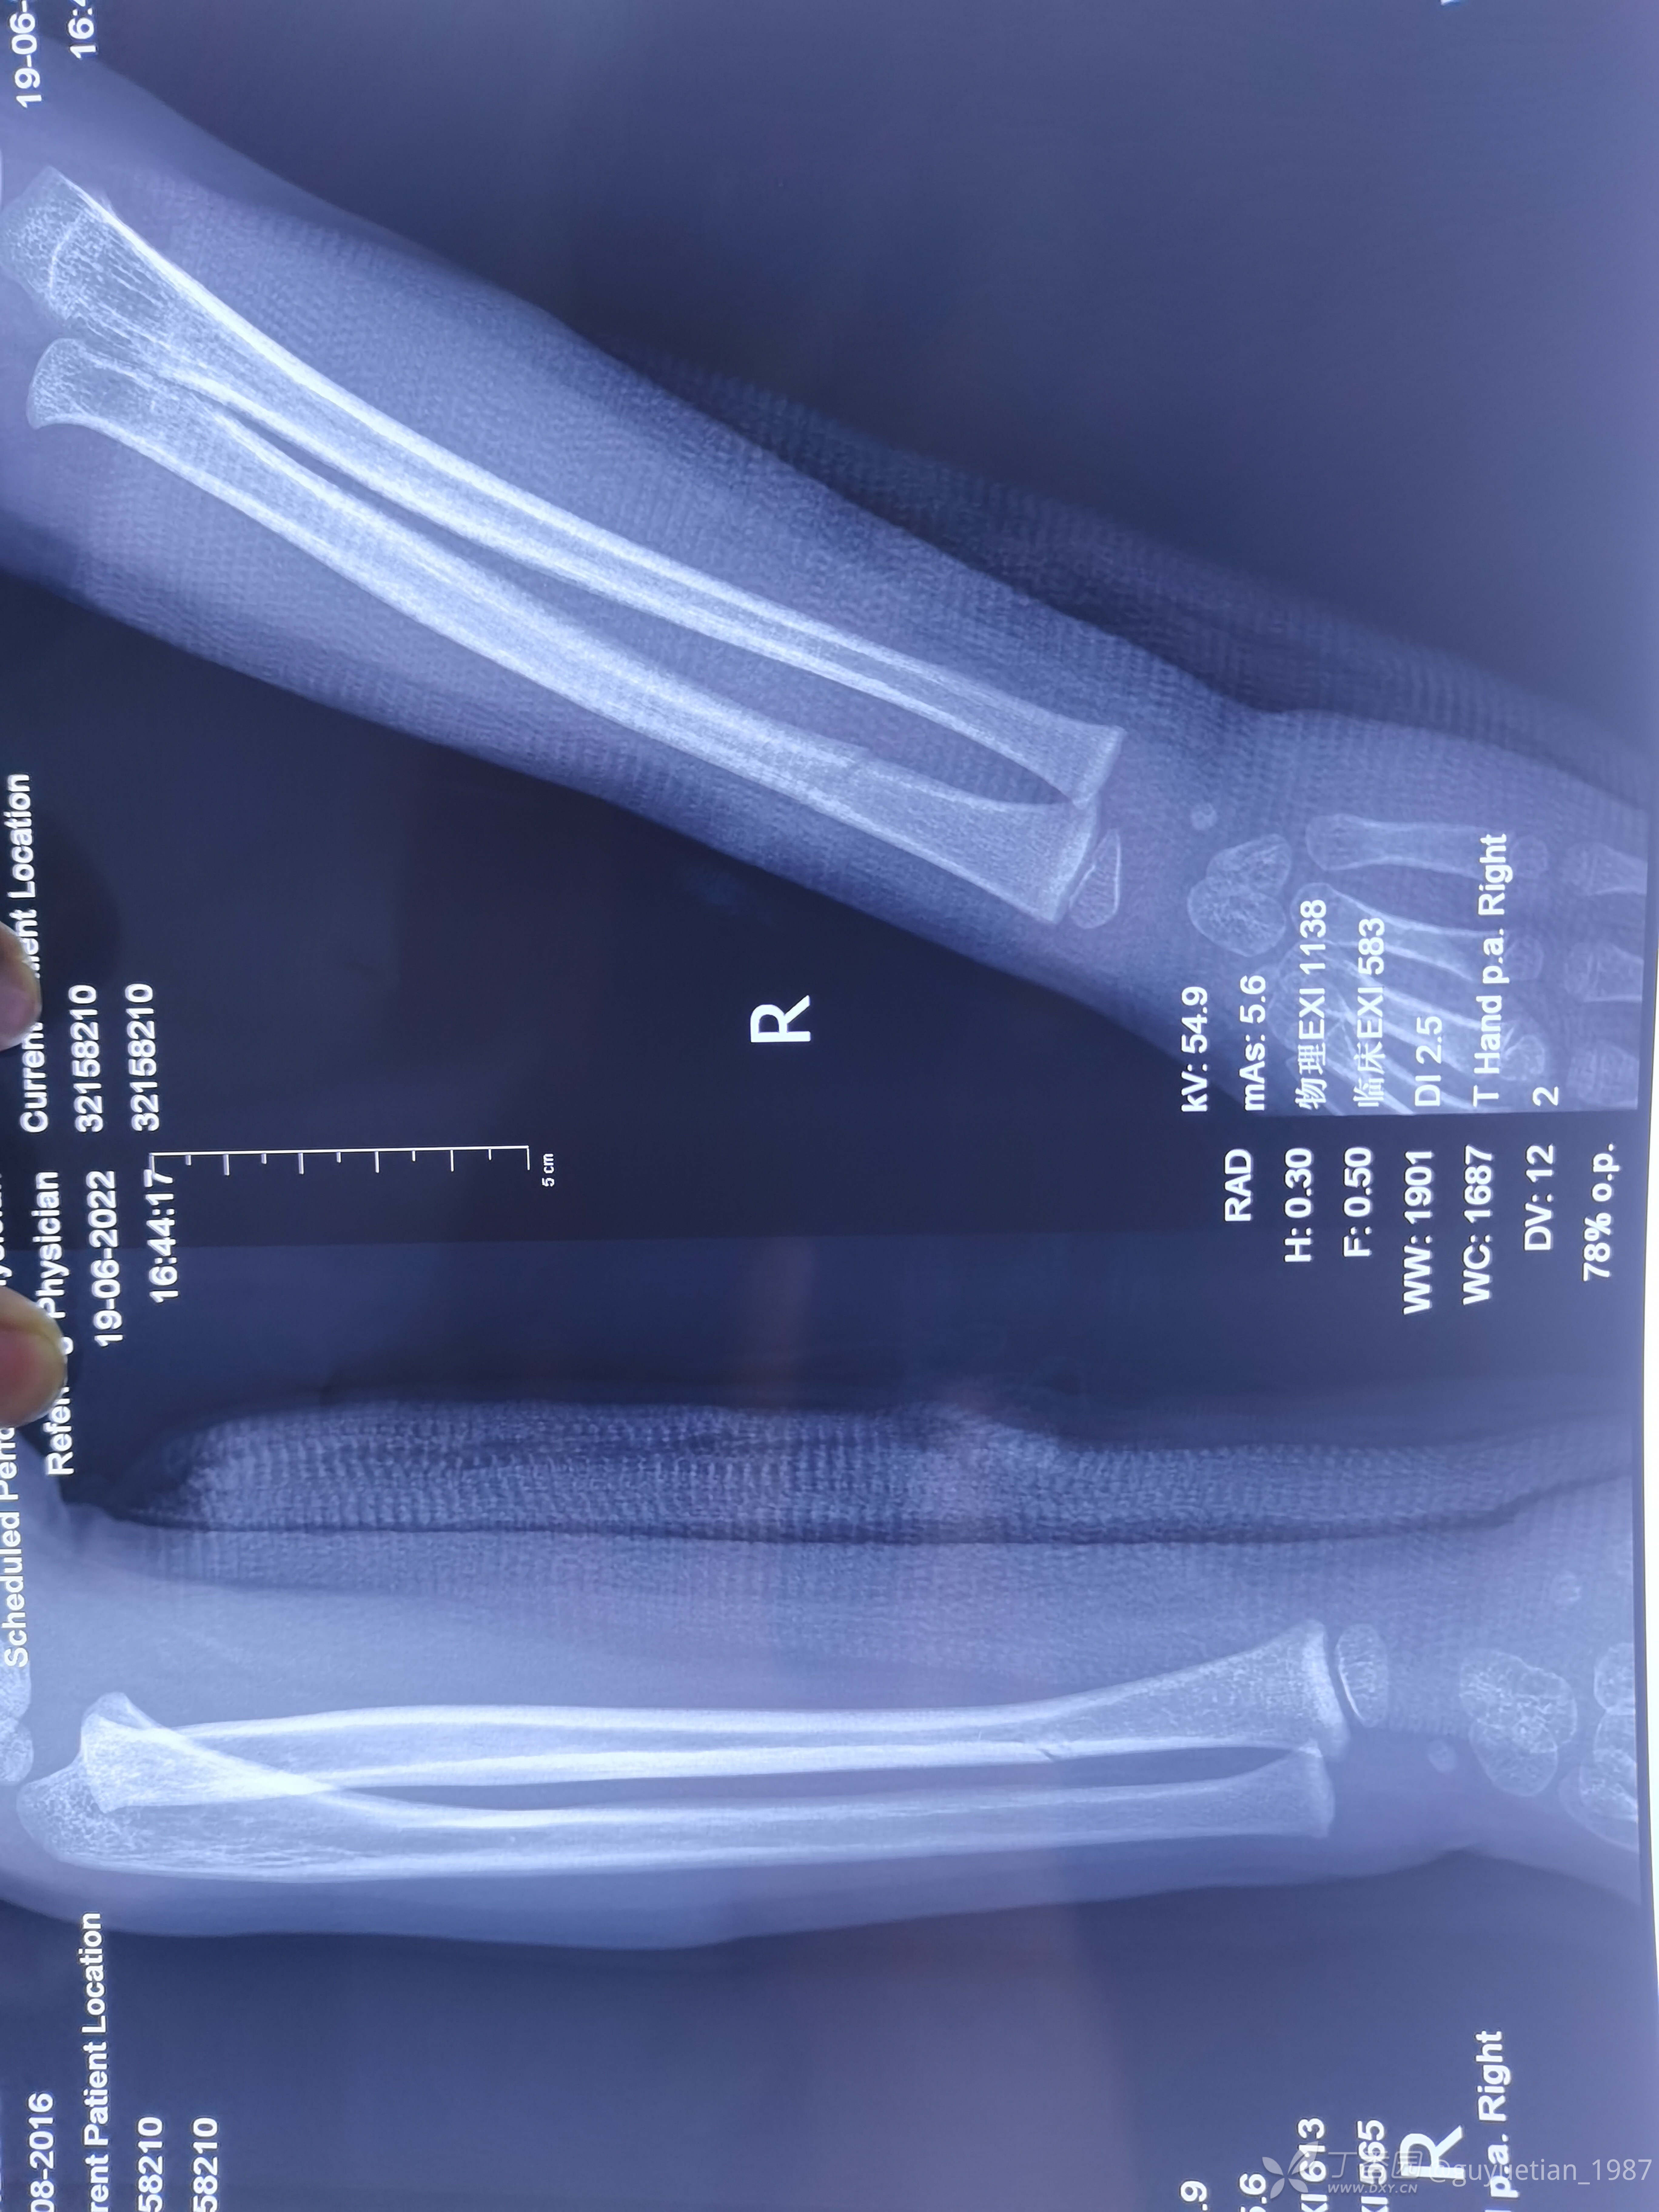

然后就是一周后复诊,侧位像背侧成角。门诊医生斩钉截铁告知这样的位置必须要手术治疗。犹豫后又电话联系再次找到我,再次纠正力线,背侧加了块压垫。复片后力线还行,但是感觉到家属开始犹豫了(门诊是一位资深老医生,专做保守,当地小有名气,说话当然比我有分量),再次坐下来跟爸爸沟通病情,还是让他自己做出选择,手术还是保守?利弊让他自己权衡,当然个人还是希望他保守,对于这个年龄孩子能不手术尽量不要手术(心底知道保守肯定没有问题),适时掏出手机给他看了曹老师的保守治疗典型病例给家属来颗定心丸。

2周后复诊,出现骨痂

3周后,明显看到骨痂,开始塑形。